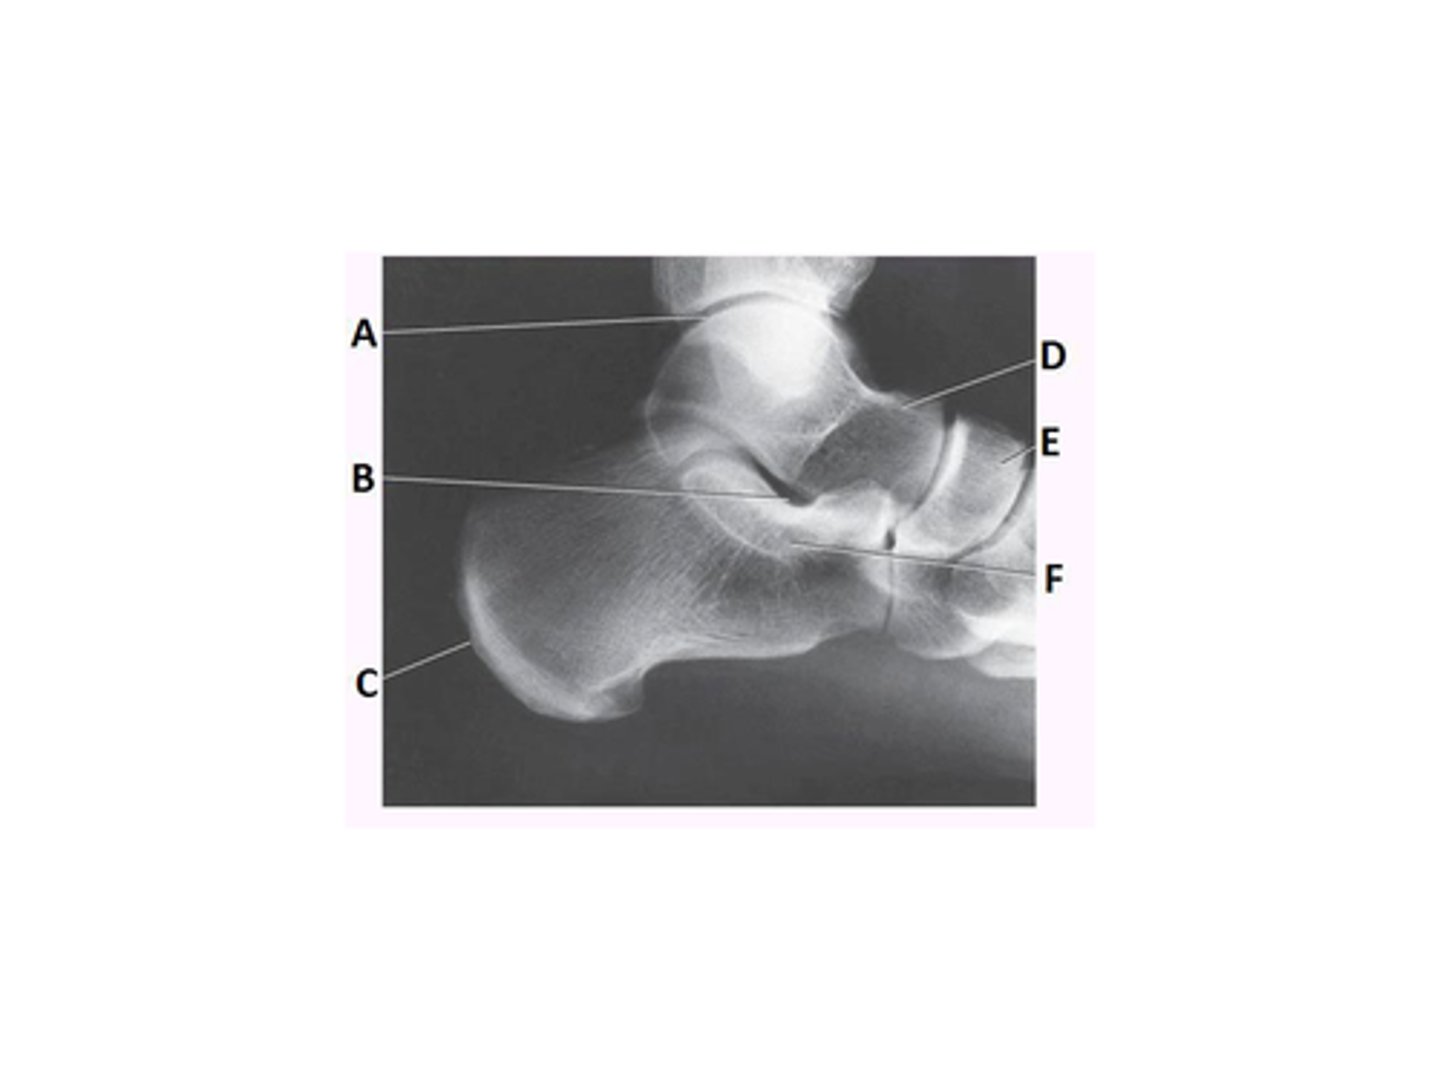

What anatomy is labeled as letter E in the image below?

Mortise joint

Tibiotalar joint

What anatomy is labeled as letter A in the image below?

Tibiofibular joint

Sinus tarsi

Tibiocalcaneal joint

Navicular

What anatomy is labeled with the letter B in the image below?

Lateral malleolus

Medial malleolus

Talus

What anatomy is labeled as letter B in the image below?

Sustentaculum tali

What anatomy is labeled as letter D in the image below?

Tibia

Fibula

Calcaneus